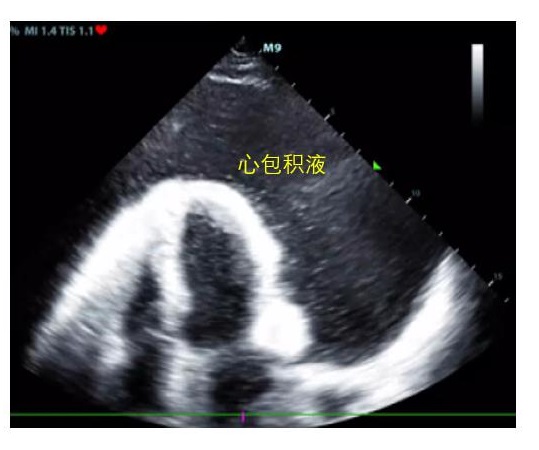

A、心包腔观察有无心包积液,及其引起右心舒张受限、心包填塞导致循环衰竭的超声证据(图 2)。此外,对于心包积液者,需谨慎观察有无主动脉增宽、漂浮的内膜片等夹层证据及心室壁不连续、异常血流通道等心脏破裂超声证据,区别主动脉夹层破裂、心脏破裂等原因引起的心包积血(图 3)。

| 心包腔内可见无回声液性暗区 图 2 心包积液超声表现 |